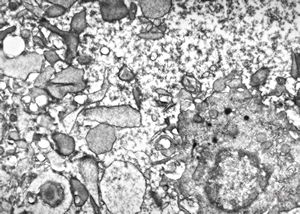

M,71y. | blood - blastic elements